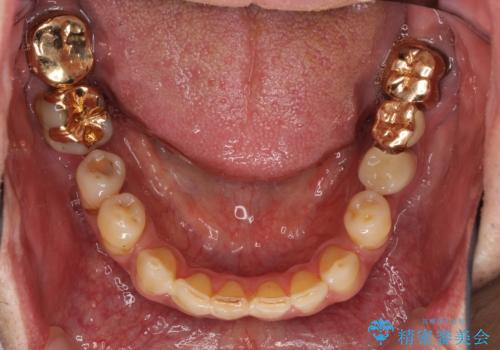

下顎の部分矯正を行ってから奥歯の補綴治療とインプラント治療

- 抜歯した歯や抜歯が必要と思われる歯を放置したため、奥歯に不快を感じているとのことで来院された患者様です。

右下は奥歯が抜歯したスペースを塞いでしまい、左下はブリッジの支台歯の1つが破折している状態でした。

また、下顎前歯にはスペースがあり、コンポジットレジンでスペースを閉じている状態だったので、前歯のスペースを解消しつつ、奥歯にスペースを獲得するよう矯正治療を行うこととしました。

並行して左下にはインプラントを埋入し、上顎臼歯部の気になる部分も根管治療などを進めて行き、矯正治療を終えると同時に補綴治療を行うこととしました。